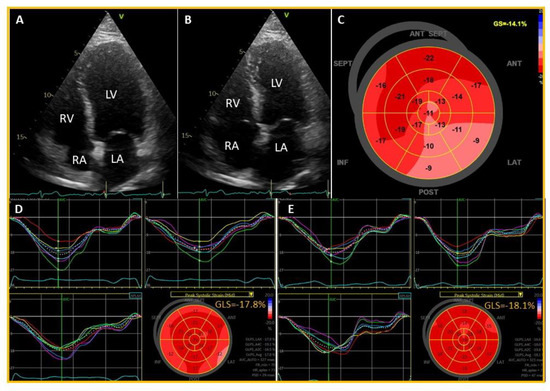

2. Case Presentation